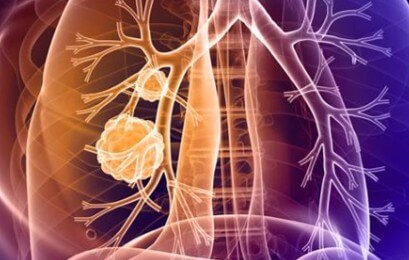

기수별 폐암 생존율에 대해 알아보겠습니다. 전이정도에 따라서 생존율이 많이 달라지게 됩니다.

- 1기: 암이 폐 한쪽에만 국한되어 있고 주변 조직이나 림프절에 전이되지 않은 경우입니다. 5년 생존율은 80% 이상으로 가장 높습니다.

- 2기: 암이 폐 한쪽에만 국한되어 있지만 주변 림프절에 전이된 경우입니다. 5년 생존율은 60-70% 정도입니다.

- 3기: 암이 폐 양쪽으로 퍼졌거나, 흉막이나 심장막, 횡격막 등 주변 조직에 전이된 경우입니다. 5년 생존율은 30-40% 정도입니다.

- 4기: 암이 먼 장기(뼈, 뇌, 간 등)로 전이된 경우입니다. 5년 생존율은 5-10% 정도입니다.